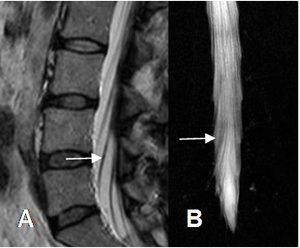

Fig 24. Cola de caballo.

A: RM sagital en T2 y B: Melografía por RM. Raíces normales de la cola de caballo que se dirigen

en forma oblicua, para salir por el agujero de conjunción correspondiente.